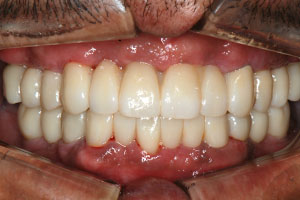

치료증례 전후사진

Before & After